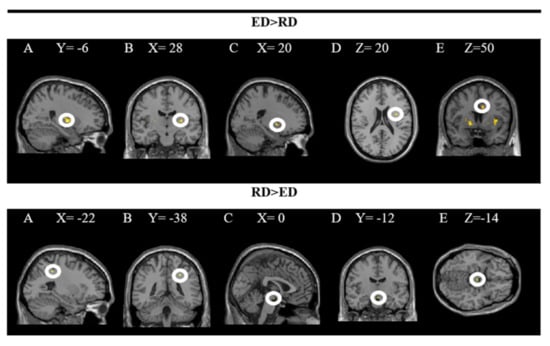

The findings showed significant activity in the following areas: L putamen, R putamen, R pallidum, R insula and R middle cingulate gyrus while processing dishes with emotional descriptions (ED × PD). The results of the inverse contrast (RD × PD) indicate greater activity in the R superior parietal and ventral DC when the dishes on the restaurant menu with a rational description (vs. emotional) are processed. In these analyses, a significance level of p = 0.005 was established without correction. The results are presented in Figure 4 and the coordinates of the peak are in Table 2.

Figure 4.

Brain regions activated more strongly to emotional vs. rational description (ED > RD) and rational vs. emotional descriptions (RD > ED).

The upper part of the figure shows a T-map with a threshold of p < 0.0001 uncorrected for multiple comparisons (T > 2.73), superimposed on the average anatomical image of all subjects (NIM-space). A: L putamen; B: R putamen; C: R pallidum; D: R insula; E: R middle cingulate gyrus. The lower part shows a T map with a threshold of p < 0.0001 uncorrected for multiple comparisons (T > 3.2), superimposed on the average anatomical image of all subjects (MNI-space). A and B: superior parietal R; C, D and E: ventral DC. See the corresponding coordinates of the peaks in Table 2.